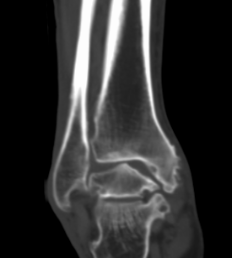

影像学检查:最重要的诊断依据:如X片检查、CT检查、MRI检查、超声波检查等,其中X片及CT对诊断尤为重要。

CT检查:提供高分辨率的骨结构影像,特别适用于评估关节内骨折和骨赘的形成情况;